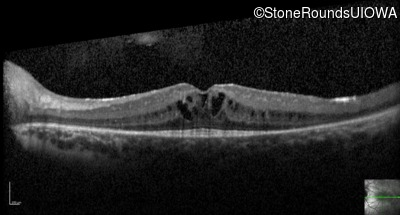

Leber Congenital Amaurosis (IA2a)

Visit at age: 7 years

Optical Coherence Tomography - Right - 20/40 -2

Exemplar / OCT Stack